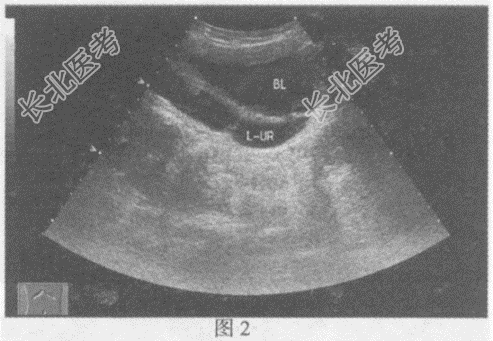

- 单项选择题临床资料:女, 9岁,自述左侧腰部疼痛2年余。

超声综合描述: 左肾增大,上极部集合系统内可见4.3cm×3.1cm无回声(图1), 形态不规则;下极部集合系统未见分离。左输尿管全程显示(图2、图3), 内径1.7~2.7cm,左输尿管末端可见一类圆形无回声区突向膀胱内(图4), 囊壁薄而清晰、规则,动态观察无回声区大小随左输尿管蠕动有节律变化。

超声提示: A、左输尿管全程扩张

B、左肾重复肾上部肾盂积水

C、左输尿管口囊肿